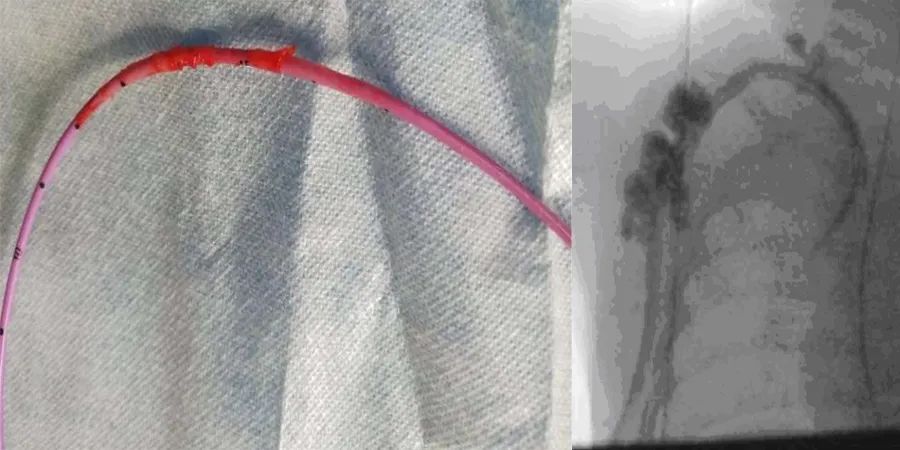

将导管更换为Medcomp®10 Fr×15 cm分离式导管®,通过一个稍微位于前一切口内侧的新切口插入右侧颈内静脉。选择大口径、短导管,以达到更高的流速和避免导管尖端的移动。影像增强确认位置,两腔在手术室冲洗和抽吸良好。放置导管后,立即尝试血液透析,但尽管冲洗良好,动脉腔仍无法抽吸,患儿明显疼痛。影像学检查显示对比剂似乎从多个部位逃逸到周围组织中(图1c)。立即取出导管,用一个位于右心房的12-Fr剥离式鞘管通过上一个切口替换成新导管。在检查或冲洗拆除的管线时,未发现断裂迹象。影像增强确认了新透析通路的位置,在肝素封管前,两个管腔在手术室抽吸和冲洗良好。

通过导管缓慢注射造影剂可以区分导管尖端血栓(造影剂喷射出导管时不规则)和导管尖端粘连血管壁(远离导管尖端的造影剂不对称或倾斜流动)。在这个病例中没有视察到这些迹象,故怀疑纤维蛋白鞘的存在。体内导管末端局部纤维蛋白鞘形成,DSA下可见沿体内导管外壁走形的线样、柱状或不规则状高密度影,包裹体内导管末端及侧孔,造影剂向上反流进入腔静脉;体内导管广泛性纤维蛋白鞘形成,DSA下可见沿体内导管外壁走形的不规则状高密度影,包裹整个或大部分体内导管,造影剂向上反流可进入植入侧皮下软组织内。纤维蛋白鞘的存在常被误认为导管破裂所致的外渗。在这个病例中,在取出导管后的检查中,没有发现管线断裂。